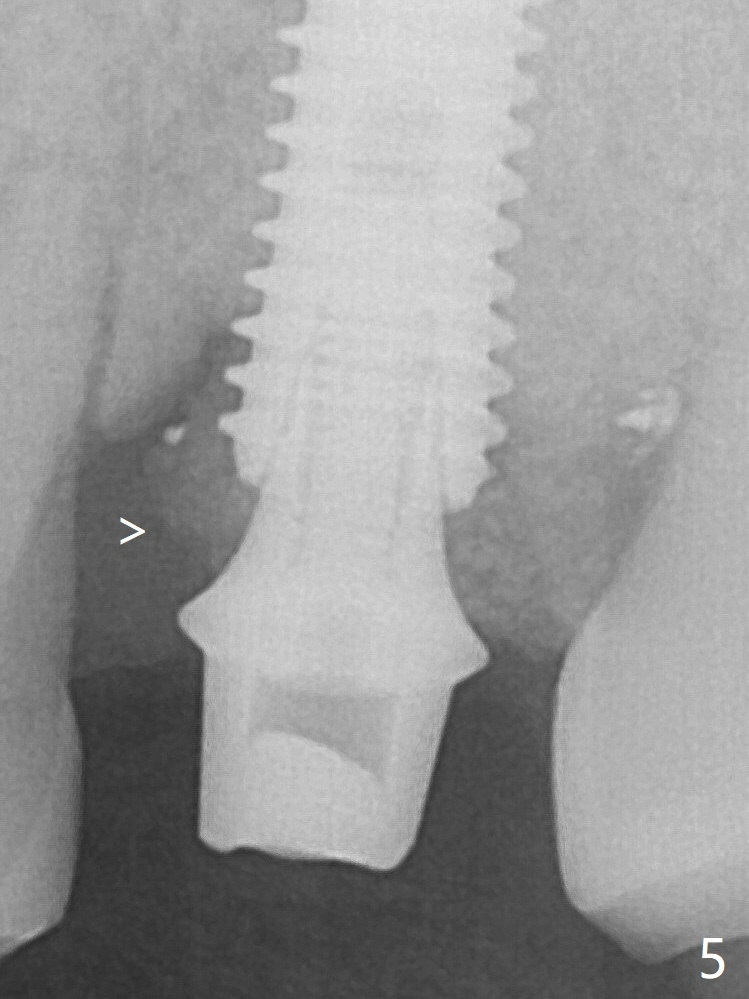

Further pushing of the bone graft from the buccal and palatal socket gaps results in more ideal packing (Fig.5 >).  If the bone graft were placed first, packing would have been easier.  An immediate provisional is fabricated to prevent further mesial shifting of the 3rd molar (Fig.1 arrow).  The implant remains stable, while the provisional and abutment are loose 3 months 1 week postop (Fig.6).  Impression is taken after abutment cleaning and retightening.